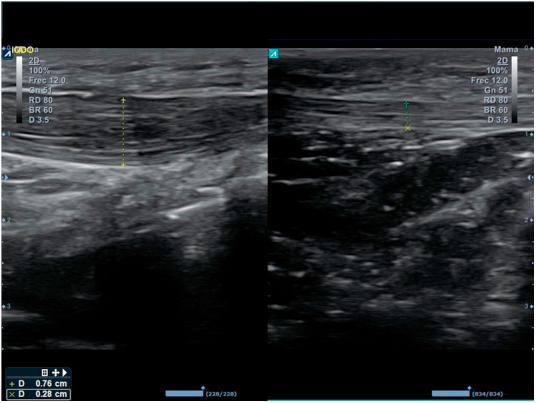

Musculoskeletal ultrasound (MSU) is a technique which has been extended to practically all medical specialties that comprise this pathology. Family Doctor (FD) has not been away from this process due to its great wide of competences, using it in different scenarios inside his common practice in which he can get profits in a reliable, efficient and effective way. Ultrasound equipment incorporation in Primary Care (PC) centers is an increasing reality, contributing to high ranges of accessibility, immediacy and clinic handle capability, and thus, together with the high prevalence in this area in locomotor apparatus, turns MSU into an strategic action for the improvement of the resolving capacity and consequently for the health care. To ensure proficiency among users, it's being necessary to define the benefits and potential risks its use can cause, as well as its different scenarios, avoiding unnecessary explorations and optimizing the investment of this resource at PC level. This paper pretends to summarize the state of the art of the musculoskeletal ultrasound and its benefits for the FD into this efficient and effective scenarios.

肌肉骨骼超声(MSU)是一种已被应用于几乎所有涉及该病理学的医学专业的技术。家庭医生(FD)因其广泛的能力范围也参与到了这一进程中,在其日常诊疗的不同场景中使用该技术,从而能够以可靠、高效且有效的方式从中获益。超声设备在基层医疗(PC)中心的应用日益普遍,这有助于提高可及性、即时性和临床处理能力,因此,鉴于运动系统在该领域的高患病率,肌肉骨骼超声成为提高诊断能力进而改善医疗保健的一项战略举措。为确保使用者的专业水平,有必要明确其使用可能带来的益处和潜在风险,以及不同的应用场景,避免不必要的检查,并在基层医疗层面优化该资源的投入。本文旨在总结肌肉骨骼超声的现状及其在这些高效有效场景中为家庭医生带来的益处。